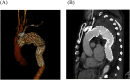

Spinal cord ischemia (SCI) is a devastating complication following thoracic endovascular aortic repair (TEVAR). A man with a ruptured thoracic aortic aneurysm (TAA) was transferred to our hospital. Emergency TEVAR, with left subclavian artery (LSA) coverage, was performed for the ruptured TAA. On postoperative day two, the patient had incomplete paralysis in his legs, presumably caused by SCI. We performed LSA revascularization (LSAR) to provide blood supply to the spinal cord; his paralysis improved and almost resolved after surgery. To our knowledge, this is the first report on LSAR's efficacy for delayed paraplegia due to SCI.